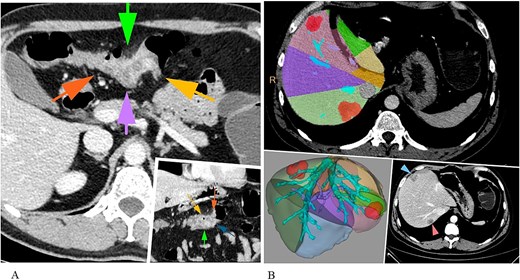

A 42-year-old male patient presented with a 2-month history of melena, and a weight loss. The laboratory examination showed anaemia: red blood cells (RBC) – 3,9 × 109/L, Hb – 8.6 g/dl. The patient’s serum levels of carcinoembryonic antigen and carbohydrate antigen 19-9 were elevated—28.3 and 47.72 U/ml, respectively. Imaging of the abdomen using computed tomography (CT) and magnetic resonance techniques revealed a tumour measuring 25 × 35 mm in the transverse colon, along with two liver lesions located in segment 7 and segment 4 inferior, measuring 35 mm and 26 mm, respectively (Fig. 1).

CT abdomen revealing a primary colon tumour (A) and liver metastases (S7, S4inf) (B).